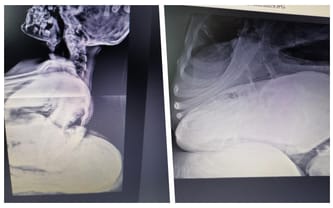

Pojechaliśmy do Warszawy, by poddać się operacji i, niestety zablokował nas COVID. Z kolei przy drugim podejściu okazało się, że czas, podczas którego gromadziliśmy środki na operacje nóżek Zuzi, sprawił, że jej kręgosłup wygiął się na tyle mocno, że żaden anestezjolog nie wyraził zgody na operację z uwagi na ogromne ryzyko i niebezpieczeństwo... Na wizycie w lipcu usłyszeliśmy, że jedyną szansą jest dla niej skomplikowana operacja w USA.

Zuzia została uznana za wyjątkowo skomplikowany przypadek i tylko dzięki cudowi, że może jeszcze oddychać. Przedstawiono nam wstępny plan leczenia - Zuzię czeka pół roku rozciągania w specjalnym aparacie skóry i kręgosłupa. Będzie to przygotowanie przed operacją... Niestety, upływający czas działa na jej niekorzyść. Doktor Feldman kazał przygotować nam się na każdą ewentualność...